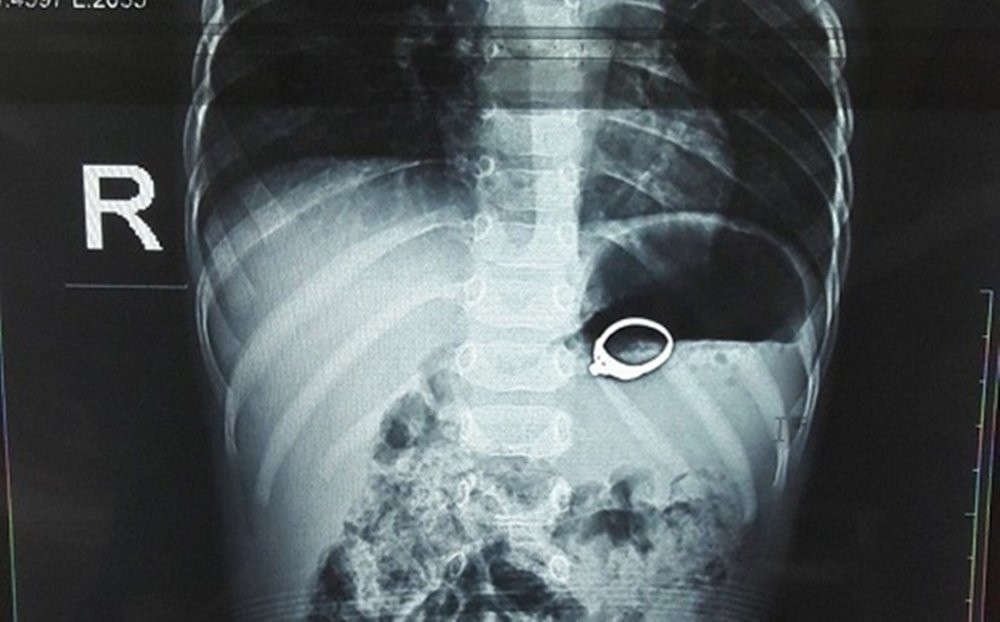

Hình ảnh dị vật là chiếc nhẫn trong dạ dày bệnh nhi 13 tháng tuổi ở Nghệ An. (Ảnh: BVCC)

Kết quả thăm khám cho thấy, dị vật là chiếc nhẫn nằm sâu trong dạ dày bệnh nhi. Nguy hiểm hơn, chiếc nhẫn có cấu tạo đính đá gồ trên mặt, dưới sự tác động của co bóp dạ dày nên đã gây xước niêm mạc, xung huyết dạ dày người bệnh. Ngay lập tức, bệnh nhi được chỉ định can thiệp loại bỏ dị vật. Rất may sau đó, chiếc nhẫn được lấy ra an toàn, sức khỏe của bệnh nhi được bảo toàn.